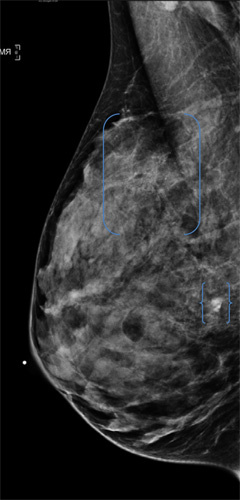

[Caption above and below:Mammography images (from 2010, left; and 2012, right) of a woman in her forties with no family history of breast cancer who missed a year of screening and in the interval developed suspicious right upper out calcifications [ ] and a suspicious mass { }, both of which underwent biopsy, yielding invasive carcinoma.]

Photo Source: Radiologic Society of North America RSNA